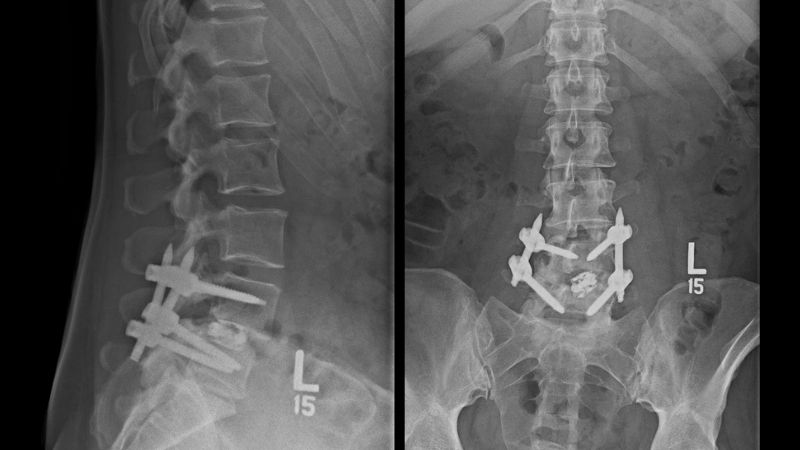

Quirúrgico

- Cirugía

- Ultima alternativa en dolor lumbar crónico, inespecífico con discapacidad asociada que no responde a tratamiento conservadores.